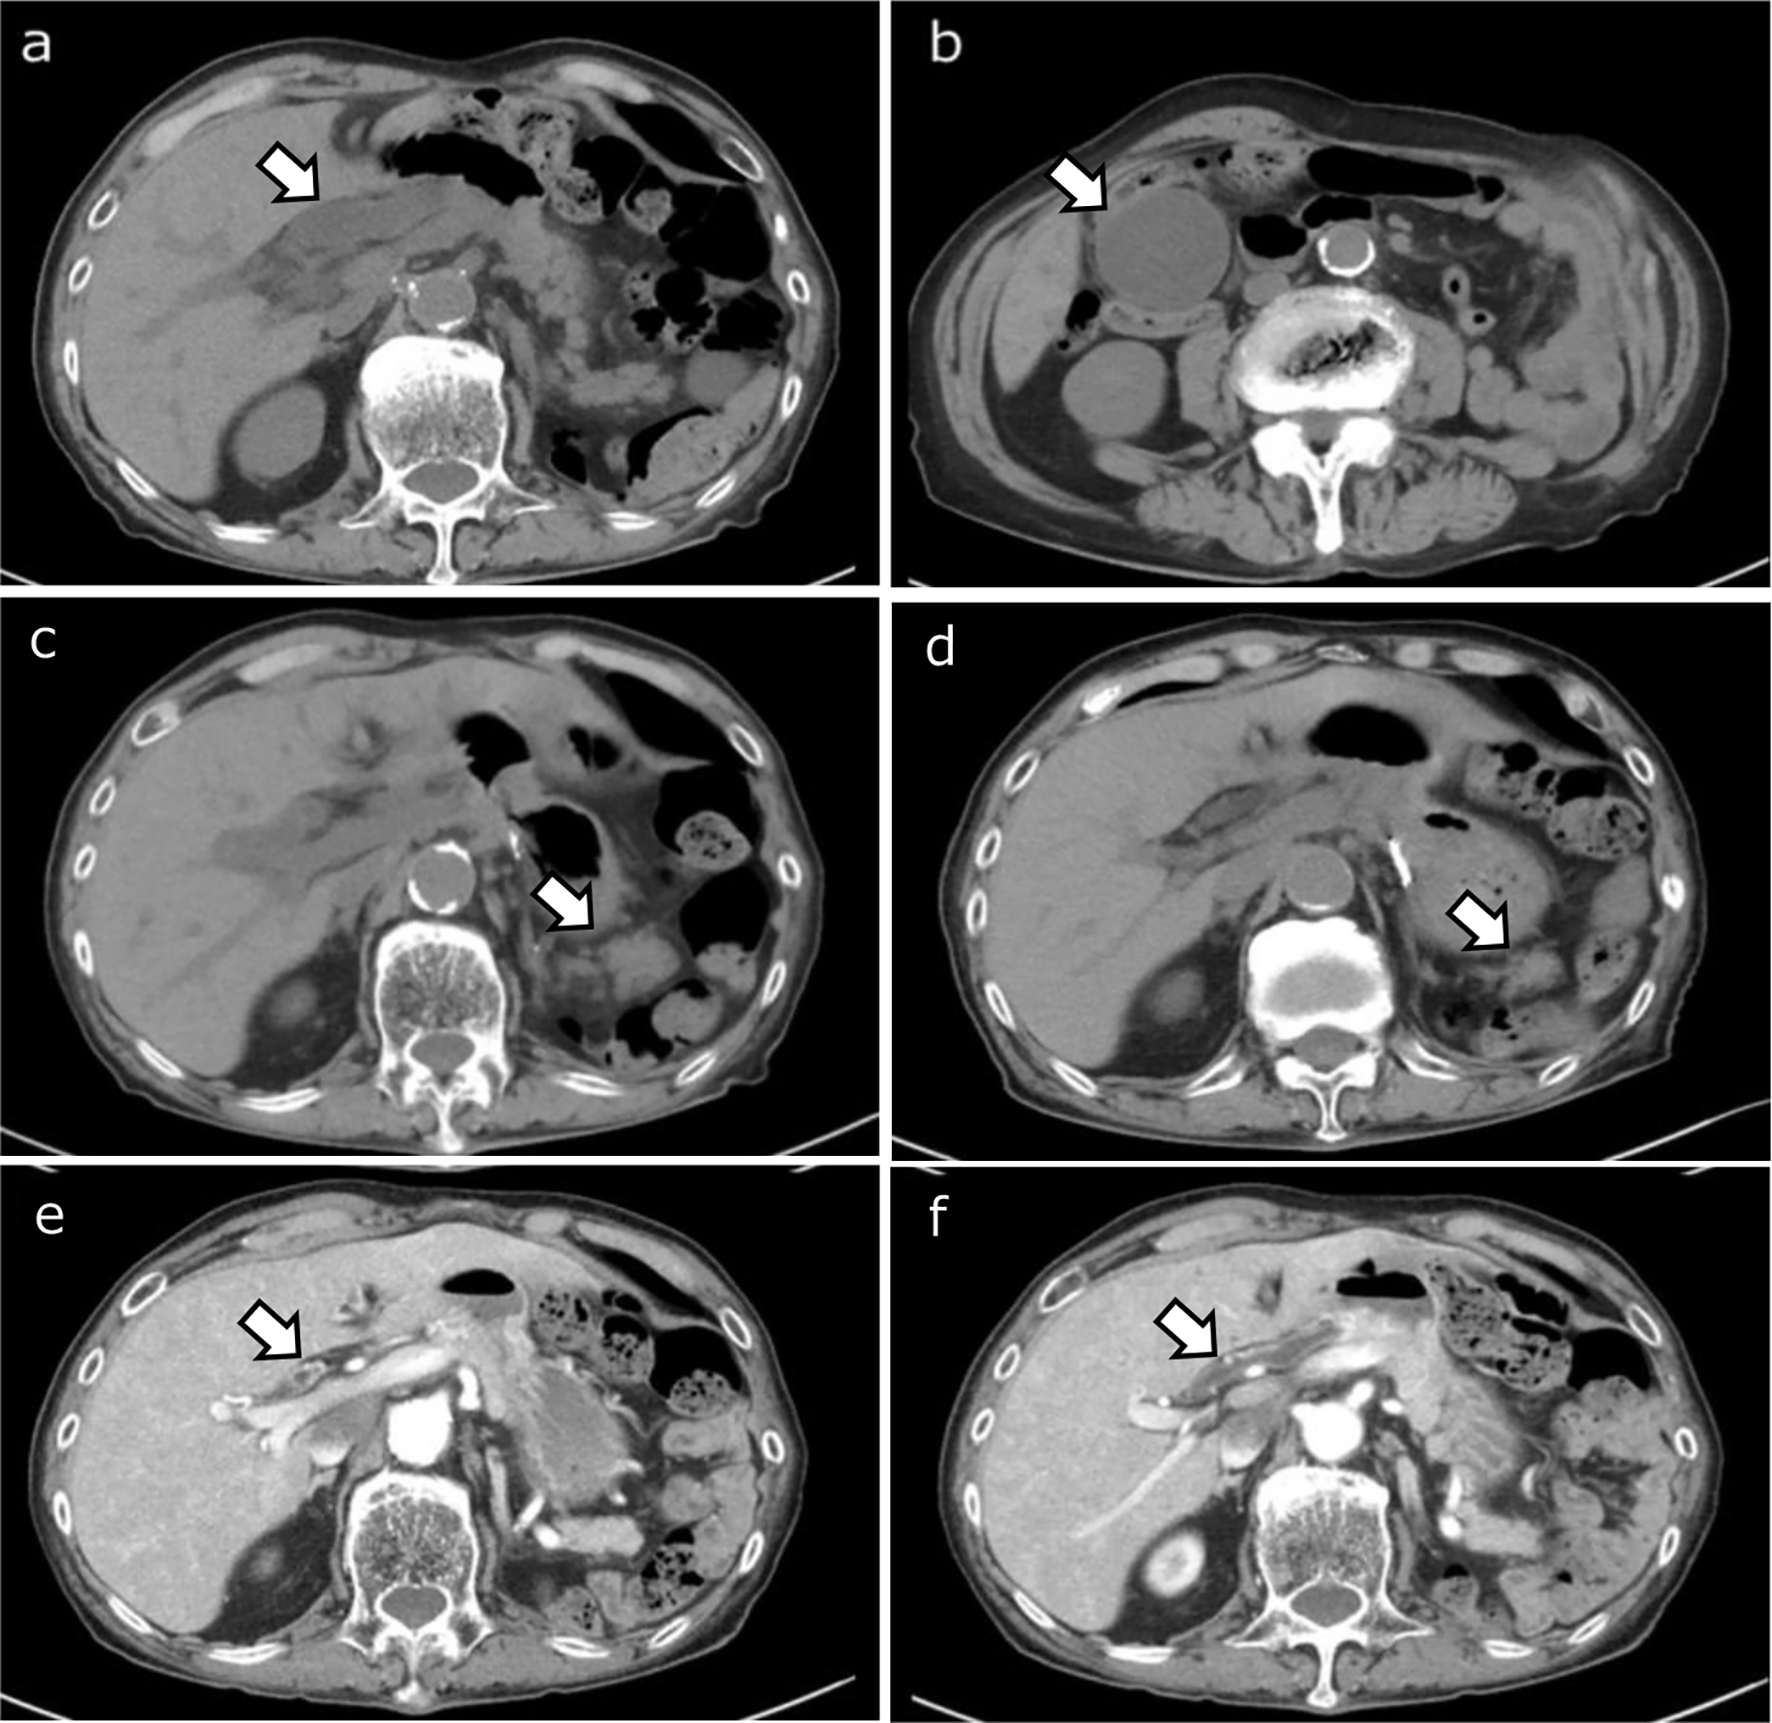

Prior research has indicated that fibrosis progression may be more pronounced in the medial segment (S4) of the left lobe and the anterior segments (S5, S8) of the right lobe compared to other segments [4]. Morphological changes associated with liver cirrhosis often involve atrophy of the right lobe (primarily S5–S8) and the medial segment (S4), accompanied by hypertrophy of the caudate lobe (S1) and the lateral segment (S2, S3) [22, 23]. As fibrosis progresses, it leads to an expansion of the extravascular extracellular space and a relative reduction of the intravascular space within the affected tissue. This suggests that fibrosis might progress earlier in regions prone to atrophy, leading to an earlier increase in fECV in these areas. To substantiate this hypothesis, future research is needed to quantitatively measure the volume of each segment and directly verify the correlation between the degree of atrophy and fECV values. Consistent with this hypothesis, our study found that in mALBI grade 2a, fECV was significantly higher in S4, S5, and S8 compared to other segments. In the more advanced mALBI grades 2b and 3, where fibrosis has likely progressed throughout the liver causing global functional decline, significant differences in fECV among segments were no longer observed. The lack of significant inter-segmental fECV differences in mALBI grades 2b and 3 is likely because fibrosis had progressed throughout the entire liver parenchyma, leading to a comprehensive decline in liver function that obscured the relative differences between segments. This suggests that fECV in specific segments may be a sensitive indicator for particular stages of liver function decline.

These findings highlight the importance of considering segmental variations in fECV relative to the mALBI grade. Notably, the fECV values of potentially atrophic areas—specifically the medial (S4) and anterior (S5, S8) segments—were significantly higher in mALBI grade 2a, demonstrating their usefulness in detecting early-stage liver function decline. ROC analysis further supported this, showing that S4, S5, and S8 yielded the highest AUCs (0.968, 0.948, and 0.932, respectively) for differentiating mALBI grade 1 from grade 2a or higher. This segmental pattern is also visually evident in representative cases, as shown in Fig. 6. In particular, the fECV map of the mALBI grade 2a patient (Fig. 6B) clearly demonstrates elevated values in the medial segment (S4), supporting the notion that early fibrosis-related functional decline may be regionally accentuated. These findings suggest that fECV in these regions may serve as sensitive biomarkers for early disease progression. In contrast, while the AUCs for the posterior segments (S6, S7) were relatively lower in early-stage prediction, only these segments exhibited statistically significant increases in fECV across all consecutive mALBI grades. This trend indicates that fECV in S6 and S7 may be better suited for evaluating the stepwise progression of hepatic functional impairment. However, we acknowledge that comprehensive stratification of liver disease severity may require whole-liver assessment, and further validation is needed to establish the prognostic value of segmental fECV. Taken together, our results imply that fECV provides complementary clinical value depending on the hepatic segment evaluated—serving both as an early detection tool (S4, S5, S8) and a staging marker for disease severity (S6, S7). The ability to examine fECV in each liver segment highlights an advantage of CT. Liver biopsy is limited to specific regions, and its invasiveness precludes multi-segment evaluation [24, 25]. Elastography techniques (ultrasound or MRI) are often restricted, primarily to the right lobe, due to technical challenges and artifact susceptibility, making comprehensive whole-liver assessment difficult [26, 27]. CT, however, offers advantages such as rapid acquisition, relative ease of performance, and reduced motion artifacts, enabling segmental fECV evaluation. It is important to position the clinical utility of segmental fECV not as a replacement for, but as a complement to established blood-based markers such as the mALBI grade. While mALBI provides a reliable and cost-effective measure of current liver function, fECV offers insight into the underlying structural pathology—namely fibrosis—that drives future, irreversible decline. Its potential lies in serving as an early predictive biomarker. Moreover, because contrast-enhanced CT is routinely performed for indications such as HCC surveillance, fECV can be calculated opportunistically without additional cost or radiation exposure. Unlike global blood tests, segmental fECV enables mapping of spatial heterogeneity, which may refine clinical decision-making—for example, by guiding biopsy to the most fibrotic regions or informing preoperative planning for hepatic resections and locoregional therapies.